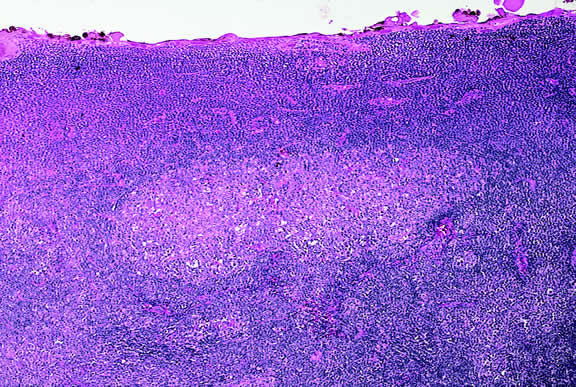

Lymphoma

Although non-Hodgkin's lymphoma often affects the orbit and conjunctiva, intraocular involvement by lymphoma is relatively rare and occurs in two basic ways. First, patients who have widely disseminated systemic lymphoma may develop secondary ocular involvement whose typical manifestation is uveal infiltration. Second, in the variant of central nervous system (CNS) lymphoma that has been called primary lymphoma of the CNS and retina, the vitreous characteristically is involved and the uvea is spared. The latter entity also has been called vitreous large cell lymphoma or ocular “reticulum cell sarcoma.”205–208 In addition to the vitreous, the lymphoma cells also infiltrate the retina, and typically collect between Bruch's membrane and the retinal pigment epithelium, forming solid yellowish RPE detachments, which are highly suggestive of the diagnosis. This rare variant of primary CNS lymphoma should be suspected in older patients who have chronic vitritis that is unresponsive to therapy. Cytologic examination of diagnostic vitrectomy specimens reveals a highly cellular and extensively necrotic infiltrate that contains atypical lymphocytes with prominent nucleoli and protrusions of the nuclear membrane (Fig. 53). The significance of elevated vitreous interleukin 10 levels as a diagnostic marker for lymphoma is controversial.209,210

Fig. 53. Primary central nervous system lymphoma, vitreous. Diagnostic vitrectomy specimen contains large atypical lymphocytes, necrotic lymphoid cells, and nuclear debris. Lymphoma cells in inset have nuclear membrane protrusions and prominent nucleoli. Main figure, Millipore filter. (Hematoxylin-eosin, × 250.)

Many patients who undergo diagnostic vitrectomy to exclude lymphoma actually are found to have a form of granulomatous vitreitis termed idiopathic senile vitritis.211 Cytologically, the latter lacks necrosis and contains a mixture of well-differentiated lymphocytes and epithelioid histiocytes with a spindled or dendritiform configuration. Careful cytologic screening and follow-up are warranted in such cases, however, because vitreous lymphoma occasionally presents with chronic inflammation. Imaging studies and spinal fluid examination should be performed to exclude CNS involvement if vitreous lymphoma is diagnosed.206 CNS lymphoma may produce dementia and other neurologic signs. The prognosis is poor with a mean survival of 22 months. Intraocular Whipple's disease may mimic vitreous lymphoma.212,213